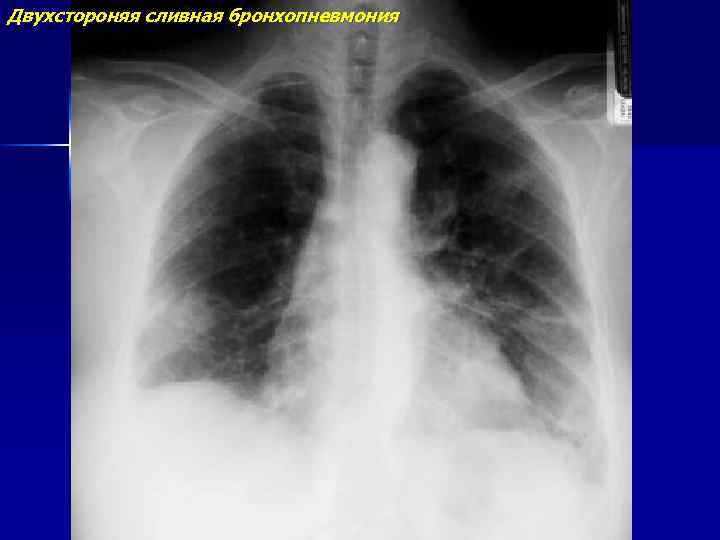

Двухстороняя сливная бронхопневмония